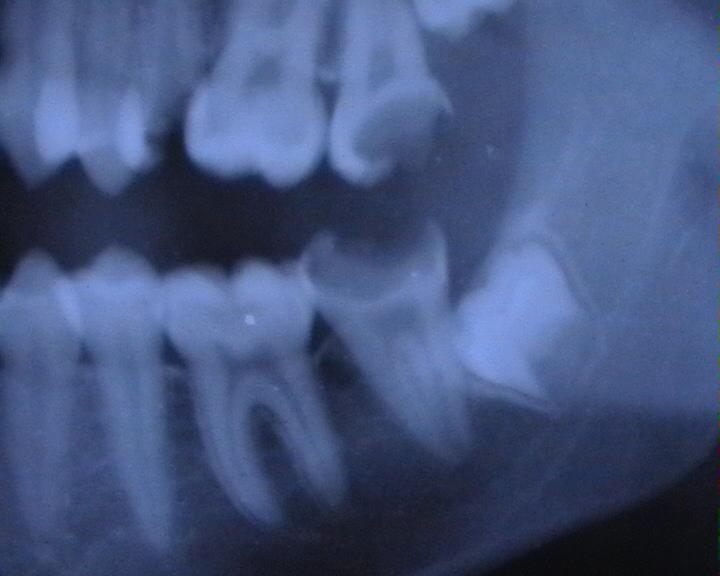

La principale affection dentaire sont les caries. Cette lésion dentaire est apparu chez l’Homme pendant le néolithique. Elle résulte d’une infection liée à des bactéries se nourrissant du sucre suite à l’évolution de notre alimentation. De nos jours, ce serait plus de 2,3 milliards d’humains qui seraient confrontés aux caries. Plusieurs techniques permettent d’endiguer la progression de celles-ci, limitation de la consommation de produits sucrés, détartrage et une hygiène buccale via un brossage régulier et un apport en fluorine.

Une fois la carie installée, il n’existe pas pour l’instant d’autre alternative que de gratter la partie de la dent affectée puis de remplir celle-ci avec un amalgame dentaire. Plusieurs axes de traitement sont explorés au travers de vaccins et de cultures de cellules souches pluripotentes. La technique EAER (Electrically Accelerated and Enhanced Remineralisation) du King’s College London semble très prometteuse. Un courant électrique de faible intensité, insensible pour la personne soignée, est appliqué au niveau des dents. Celui-ci active un processus physico-chimique qui fait entrer le phosphate et le calcium, comblant ainsi la structure affaiblie de la dent affectée par une carie. La technique a aussi pour effet de blanchir l’émail des dents.